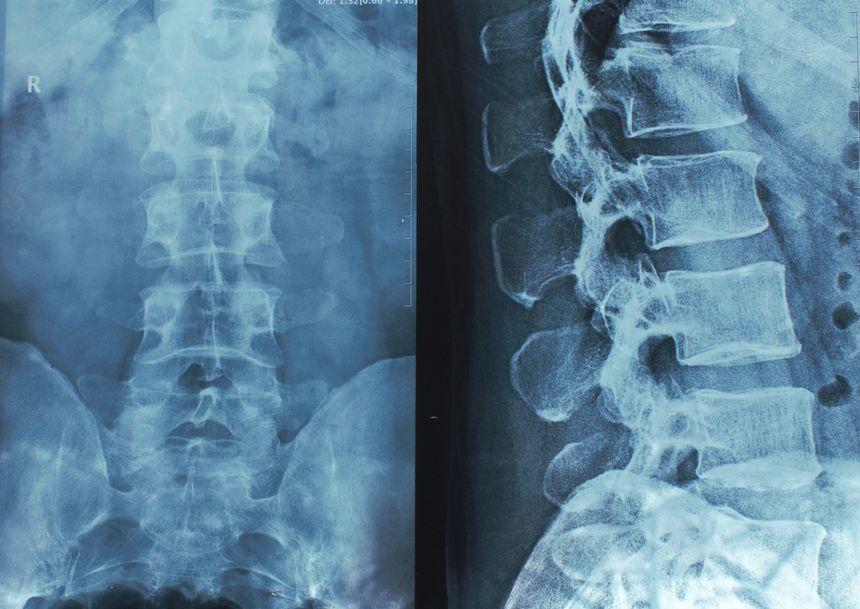

Spinal cord injuries are among the most serious medical conditions, often leading to life-altering physical, emotional, and financial challenges. While many spinal cord injuries result from accidents, such as car crashes or falls, some are caused by medical malpractice. When a healthcare provider’s negligence results in damage to the spinal cord, the consequences for a patient and their family can be devastating.

Spinal surgeries are intricate procedures that require precision. Errors such as improper placement of surgical instruments, nerve damage, or failure to address complications during surgery can result in a spinal cord injury.

Failure to diagnose conditions like spinal infections, herniated discs, or tumors correctly or timely can allow these conditions to worsen and cause irreversible damage to the spinal cord.